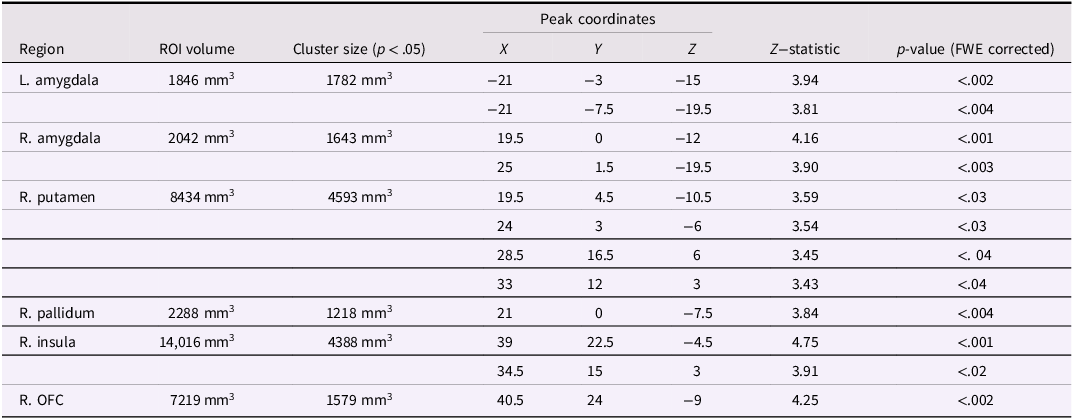

Analyses in a priori regions of interest (amygdala, nucleus accumbens, caudate, putamen, pallidum, anterior insula, and orbitofrontal cortex) revealed significant effects in bilateral amygdala, right putamen, right pallidum, right insula, and right orbitofrontal cortex. Effects in other ROIs did not survive FWE corrections across regional volumes. Coordinates and statistics for significant effects are presented in Table 3.

Table 3. VBM analysis in ROIs: significant effects surviving FWE correction in volume

Note. Significant effects represent increased gray matter associated with more severe substance use in juvenile offenders, supporting our hypotheses. FWE = familywise error correction for multiple comparisons; R. OFC = right orbitofrontal cortex.